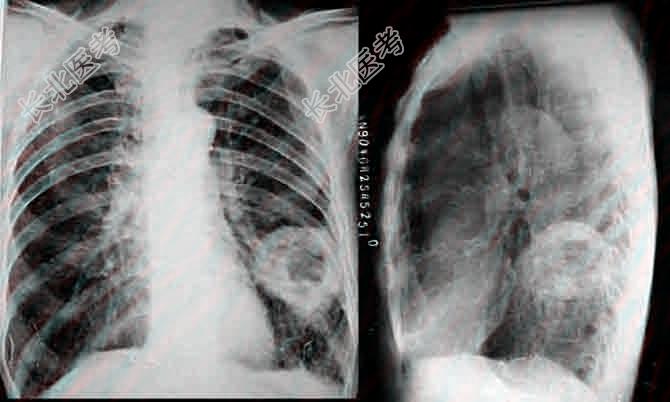

- 多项选择题5.提示:体格检查: 体温38.9℃,呼吸26次/分, 脉搏120次/分,血压120/60mmHg, 神志清,精神可, 双侧呼吸运动对称,左侧背部语颤增强, 叩诊浊音,左侧背部可闻及管状呼吸音及少量湿性啰音, 右侧无异常。心率120次/分,律齐。血常规: WBC8.7×10⁹L,NE90%, LY10%,HB121g/L, 血沉60mm/h,胸片可见左肺下叶背段片状阴影, 可见直径约4cm大小空洞影,洞壁欠光滑, 左肋膈角稍钝。如图所示。